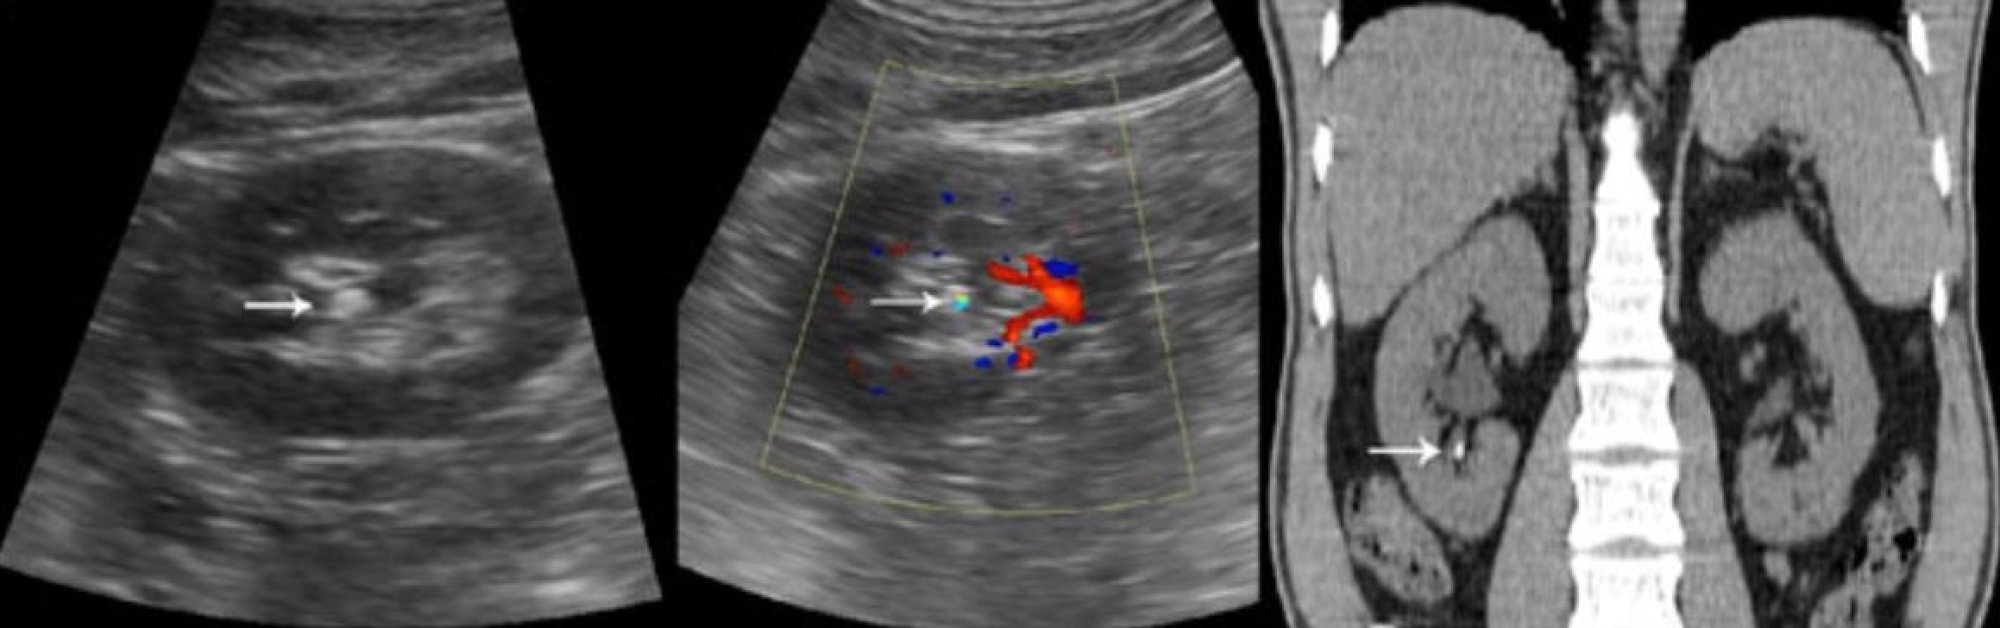

3. A Tomografia Computadorizada (TC) sem Contraste

Aqui temos o Padrão Ouro. Na urologia moderna, a Tomografia é o exame rei.

• A Vantagem: Ela vê tudo. A tomografia reconstrói o seu trato urinário em 3D. Ela nos diz com precisão milimétrica:

• O tamanho exato (sem distorções).

• A localização precisa.

• A densidade (dureza) da pedra (medida em Unidades Hounsfield).

• Por que isso importa? Saber a dureza da pedra define se vamos usar laser, litotripsia externa (quebra por ondas de choque) ou se a pedra é dura demais para certos tratamentos.